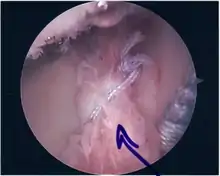

Surgical treatment of SLAP tears has become more common in recent years. The success rate for repairing isolated SLAP tears is reported between 74-94%.[7] While surgery can be performed as a traditional open procedure, an arthroscopic technique[8] is currently favored being less intrusive with low chance of iatrogenic infection.[9]

Procedure

Following inspection and determination of the extent of injury, the basic labrum repair is as follows.

- The glenoid and labrum are roughened to increase contact surface area and promote re-growth.

- Locations for the bone anchors are selected based on number and severity of tear. A severe tear involving both SLAP and Bankart lesions may require seven anchors. Simple tears may only require one.

- The glenoid is drilled for the anchor implantation.

- Anchors are inserted in the glenoid.

- The suture component of the implant is tied through the labrum and knotted such that the labrum is in tight contact with the glenoid surface.